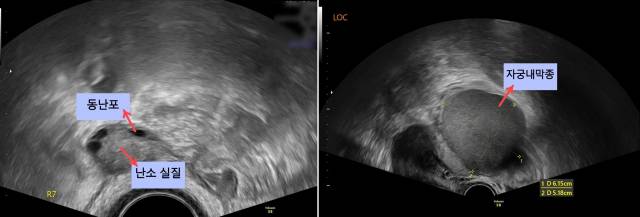

3년째 아이가 생기지 않아 불임 상담을 위해 내원한 B씨 사례를 살펴보자. B씨는 10여년 전 골반초음파에서 자궁근종을 발견했지만 심각하지 않다는 소견을 들었다. 이후 월경량이 많고 아랫배가 부푸는 느낌을 받았으나 산부인과를 찾지 못했다. 최근에서야 산부인과를 방문한 B씨는 자궁강 안에 3cm 크기의 점막하 근종이 있음을 발견했고 결국 자궁근종 절제술을 받았다. B씨처럼 자궁근종을 수술적으로 제거한 경우 자연분만이 어려울 수 있으므로 산부인과 의사와 상의해 분만 방법을 결정해야 한다. B씨는 인공수정을 시도한 끝에 임신에 성공했고 첫째를 제왕절개로 출산할 수 있었다. 참고로 임신 중에는 사용 가능한 약제가 제한적인 데다 수술도 선택적으로 결정해야 하기 때문에 자궁근종이 있다면 임신 전에 치료하는 것이 좋다.